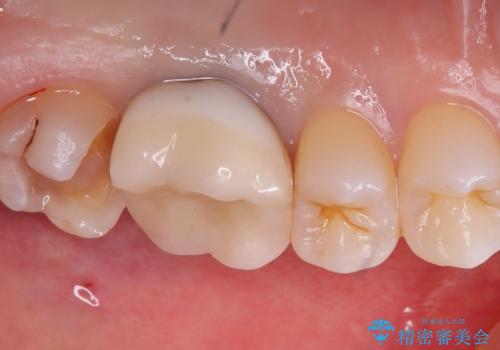

保険適用のメタルインレーを除去した際、下に広がっているカリエスも除去し形成印象を行いました。

セラミックインレーセット時はラバーダム防湿を行っています。